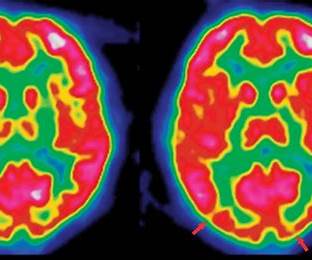

Neurobiological studies suggest differences in brain structure, connectivity, and synaptic communication in ASD. Some research points to disruptions in fronto-striatal circuits, the cerebellum, and sensory integration pathways. These neural differences may contribute to the core features of ASD (social-communication differences, restricted behaviours) and also overlap with findings in other mental-health conditions (e.g., ADHD, OCD).

A central theme is timing: early brain development autism causes emphasize events from conception through toddlerhood. During this window, synapses are formed and pruned, neural circuits are organized, and sensory-social systems take shape. Small shifts—due to genetic variants or exposures—can influence how social communication, sensory processing, and learning unfold, contributing to spectrum-level differences.